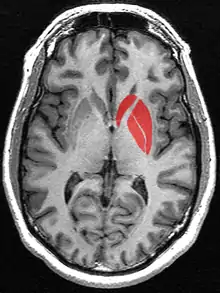

![]() Putamen (in red) shown within the brain | |

Horizontal slice of MRI-image showing the putamen. The other nuclei of the basal ganglia (caudate nucleus and globus pallidus) can be seen as well.